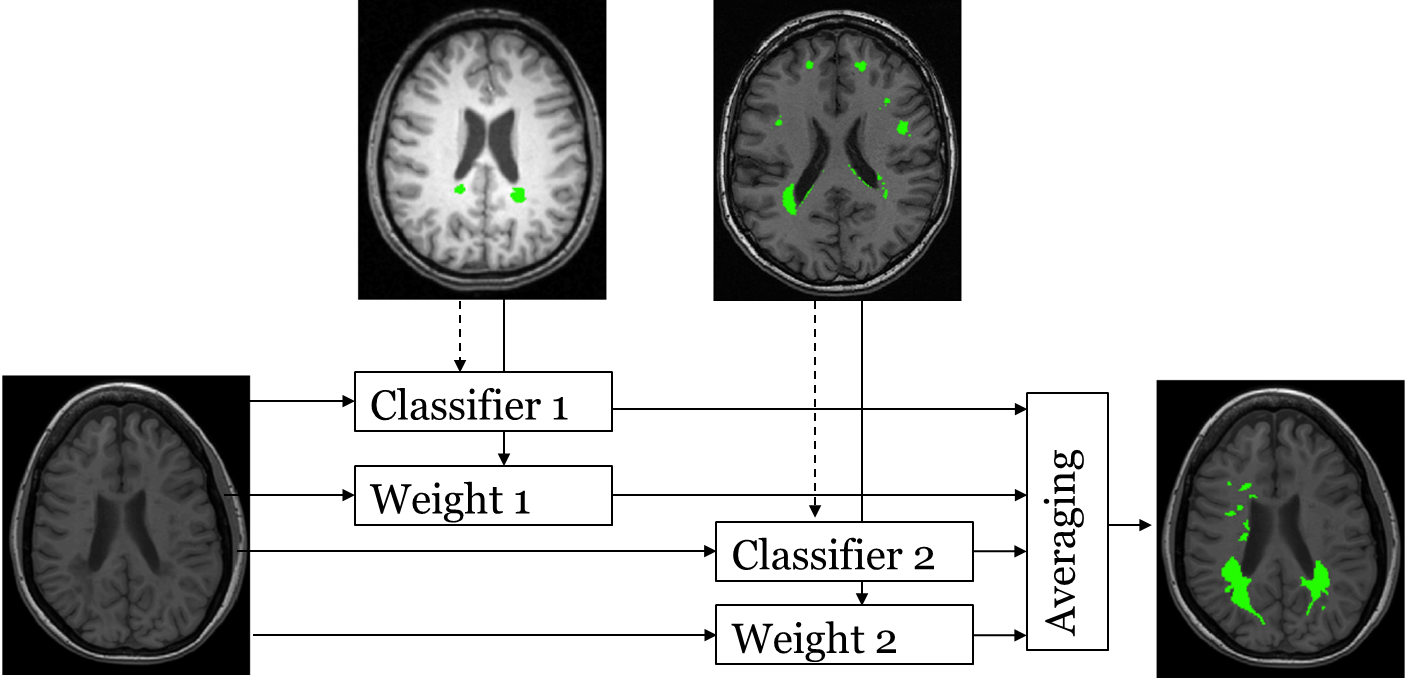

We classify each voxel by an ensemble of RFs. At test time, our method first computes the distance of the test image to each of the training images as described in Section 2.5. Each voxel is classified by each of the RF classifiers and the RF outputs are combined with a weighted average rule, where the weights are inversely proportional to the image distances. An overview of the approach is shown in Fig. 3.